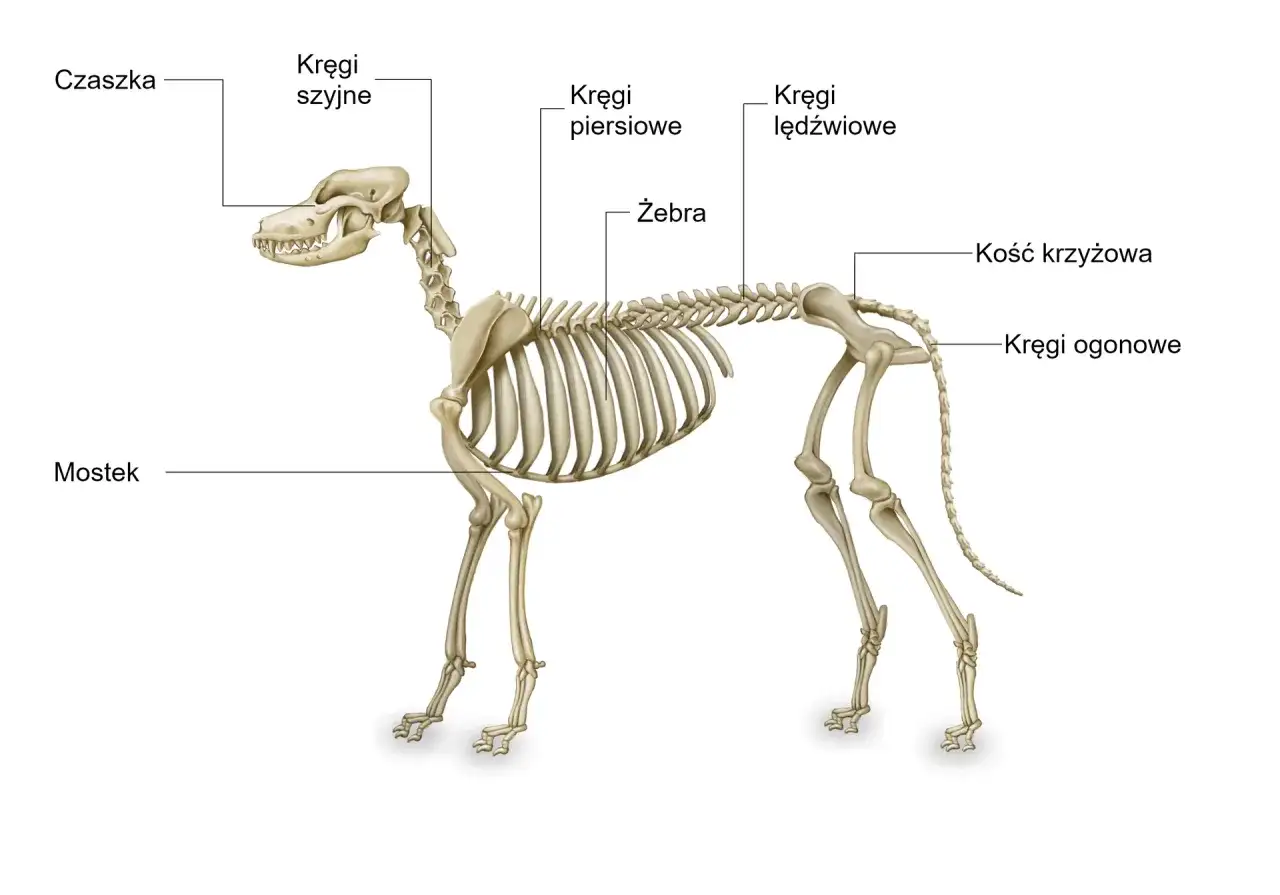

Kategoria Anatomia układu ruchu